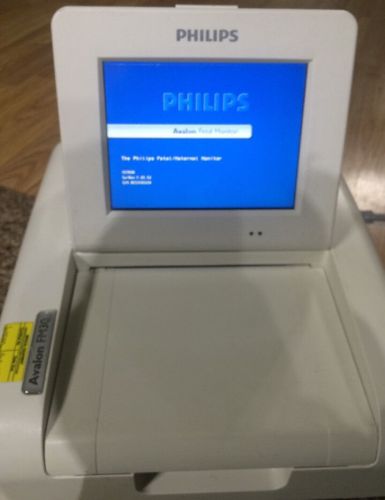

Philips M2703A Avalon FM30 Fetal Monitor